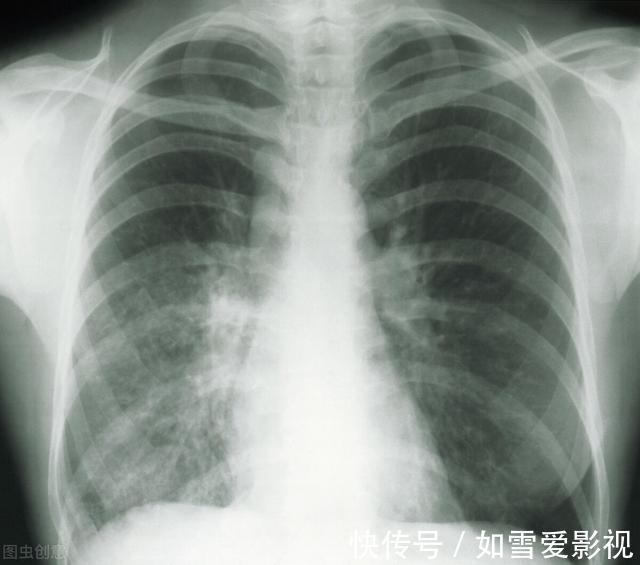

伴随了两年的“炸弹”终于解除, 陈女士心口的石头也落了地。由于发现早,手术及时,陈女士后期也无需进行放化疗。结节高发,这种肺结节需要重点关注肺磨玻璃结节一般是在做胸部CT时发现,表现为密度轻度增高的云雾状淡薄影或圆形结节,样子像磨砂玻璃,所以叫磨玻璃影。可以是弥漫性散在生长,也可以聚集在局部,看起来就像一个小磨玻璃结节。

有人把磨玻璃结节等同于肺癌,一旦患上此病,就惊慌失措。但也有人无任何不适,不以为然。其实,肺磨玻璃结节既没有那么可怕,肺部炎症、出血、纤维化(炎症后遗留的瘢痕)都可能造成这种变化,也没那么和善,更多时候它还是恶性的。所以一旦发现有肺磨玻璃结节,过分恐慌和麻痹大意都是不可取的,以下是对发现肺磨玻璃结节后处理的建议。首先,正确认识,莫恐慌。肺磨玻璃结节不一定是肿瘤,即使是肿瘤,也大都是‘早期中的早期’,有足够时间观察它的变化。专家提醒,一旦发现肺结节或玻璃结节,首先不要太害怕,在等待手术的过程中,要积极寻找治疗出路,被动等待可能会加重病情。